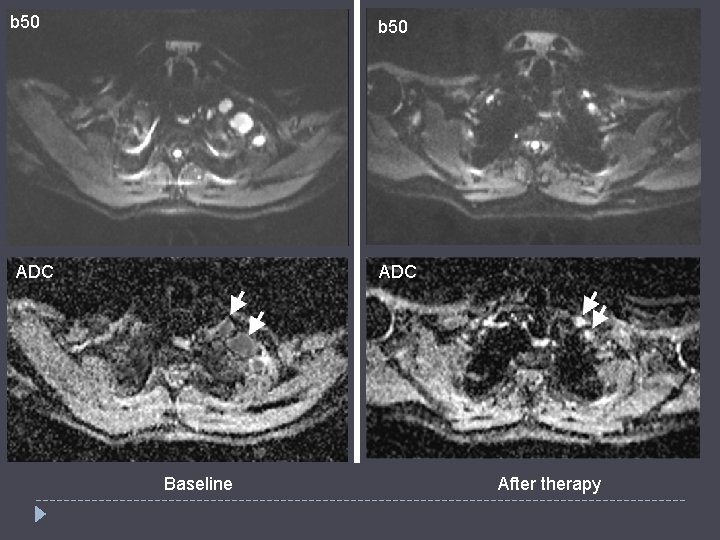

b 50 ADC Baseline After therapy

Valeur d’ADC seuil ? 29 Khoo MY, Skeletal Radiol 2011